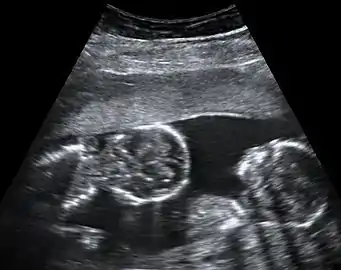

توائم ثنائية المشيمة ثنائية الكيس السلوي عمرها 8 أسابيع و5 أيام منذ الإخصاب كجزء من التلقيح الصناعي. يظهر التوأم في يسار الصورة في مستوى سهمي والرأس مشير نحو اليسار العلوي. بينما يظهر التوأم على يمين الصورة في مستوى إكليلي والرأس مشير إلى اليمين.